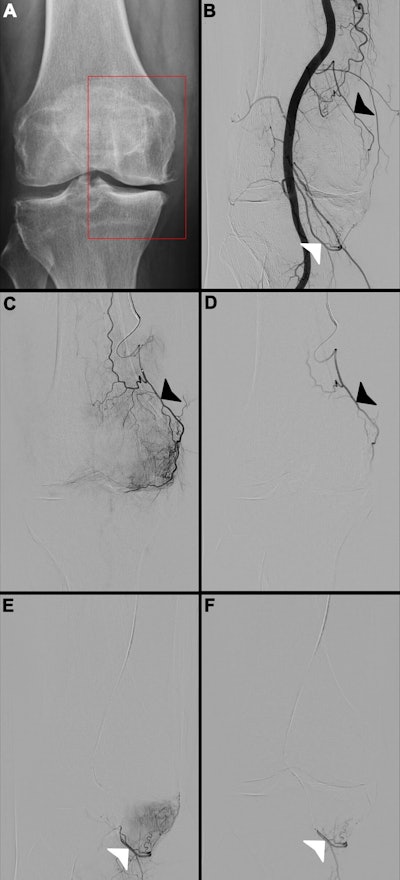

Images in a 65-year-old female patient. (A) Radiograph of the right knee shows Kellgren-Lawrence grade 3 knee osteoarthritis, with chronic pain localized to the medial compartment (red box). (B) Digital subtraction angiogram of the popliteal artery helps identify two potential target arteries: the superior medial genicular artery (black arrowhead) and the inferior medial genicular artery (white arrowhead). (C, E) Selective, pre-embolization digital subtraction angiograms of the superior medial genicular artery (black arrowhead in C) and the inferior medial genicular artery (white arrowhead in E) demonstrate a hyperemic blush in the medial compartment, indicative of pathologic hypervascularity. (D, F) Postembolization digital subtraction angiograms show successful stasis in the superior medial genicular artery (black arrowhead in D) and the inferior medial genicular artery (white arrowhead in F), with complete resolution of the hyperemic blush.RSNA